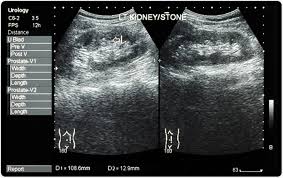

Can Kidney Stones Cause Bloody Diarrhea

Kidney stones are hard collections of salt and minerals that form in your kidneys and can travel to other parts of your urinary system.